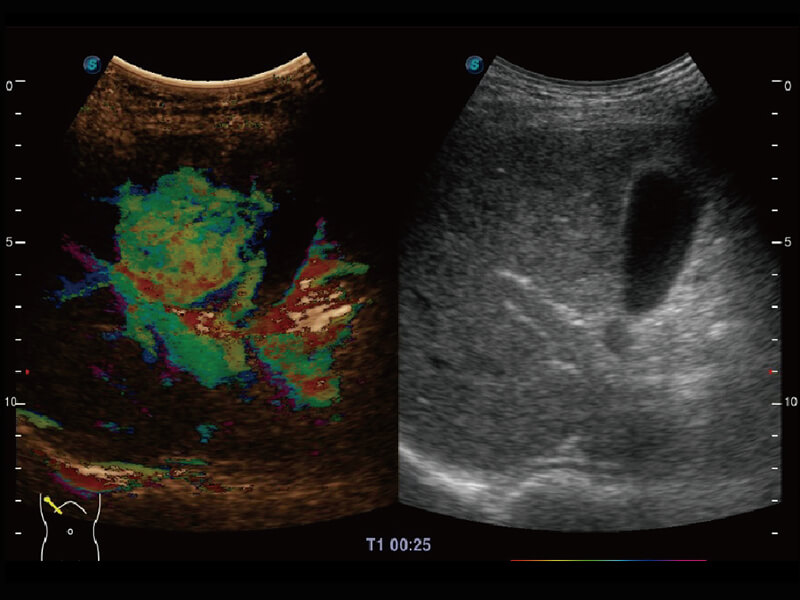

Micro F 显微血流成像 明察秋毫